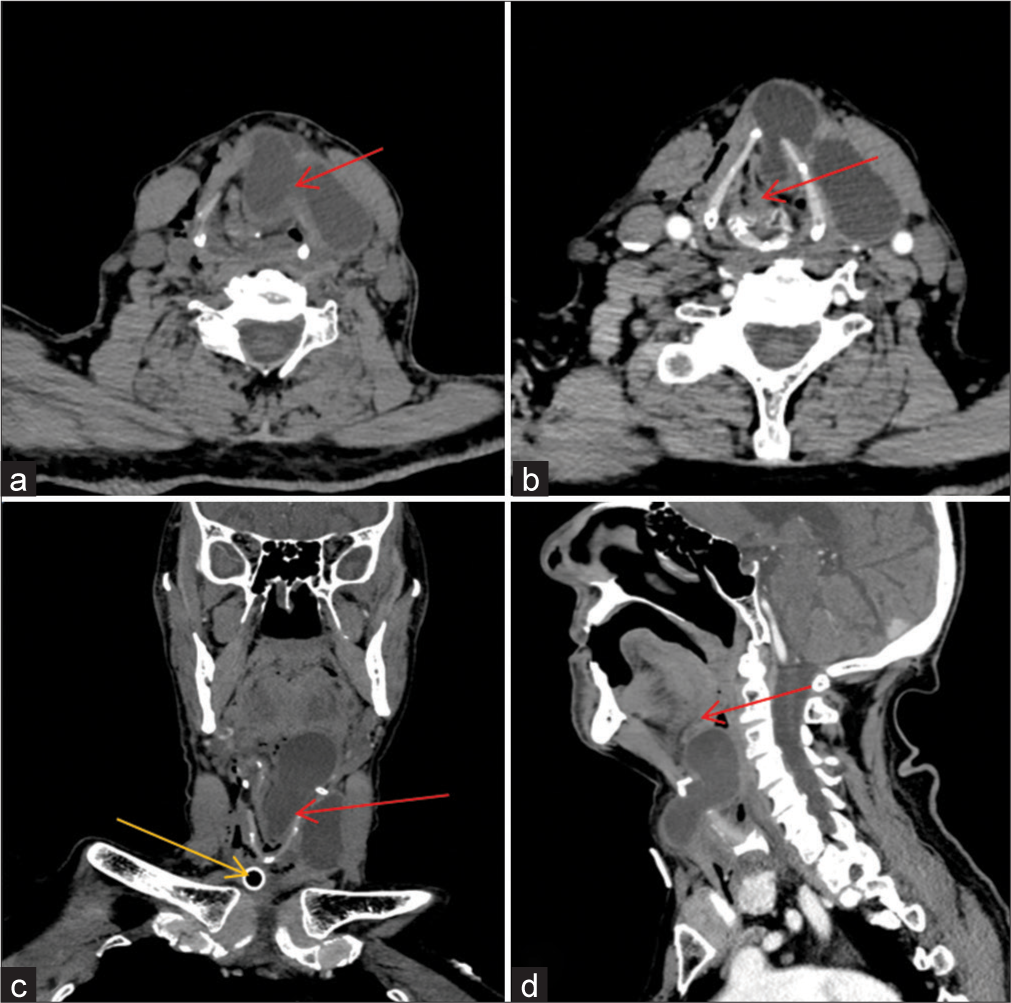

The cyst was extending into the larynx at infrahyoid level compressing the supraglottic air column through a midline defect in the thyrohyoid membrane [Figure 2a]. The intralaryngeal component measured 6.0 × 3.5 × 3.0 cm extended from C2 to C5 level. It was seen pushing the epiglottis to the right side and there was a near total narrowing of the supraglottic air column at the level of the hyoid [Figure 2b and c]. The cranial end of the intra-laryngeal extension was indenting the base of the tongue in pre-epiglottic space [Figure 2d]. Post-contrast minimal enhancement of the cyst wall was present.

- (a) Plain computed tomography (CT) scan of the neck shows a well-defined uniform cystic lesion in the anterior neck underneath the left sternocleidomastoid muscle with a breach in the thyrohyoid membrane at the infrahyoid level and intralaryngeal extension (red arrow). (b) Axial sections of contrast-enhanced CT demonstrated intra-laryngeal extension with compression of the airway column (red arrow). (c) The coronal section of contrast-enhanced CT demonstrated a breach in the thyrohyoid membrane (red arrow) and cranial extension of the cyst into the larynx. The tracheostomy tube (yellow arrow) can be seen in situ with air in the soft-tissue facial planes. (d) The sagittal section of contrast-enhanced CT shows the infrahyoid relation of the thyroglossal cyst with the intra-laryngeal component indenting the base of the tongue (red arrow).

The tracheostomy tube can be identified in situ with air foci within the soft tissue and neck facial planes consistent with surgical emphysema secondary to intubation.